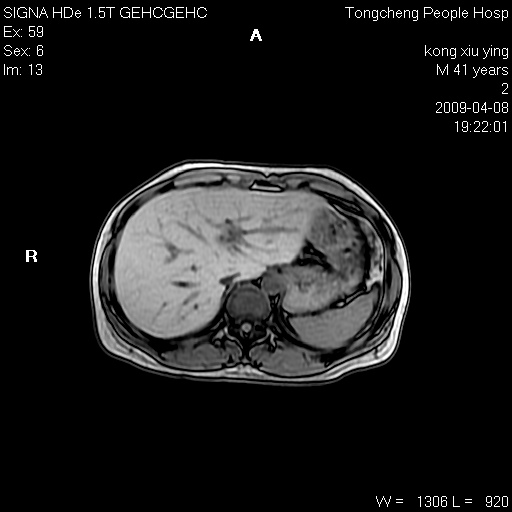

标题: CL1008:【经典】胆囊石榴籽样结石。

女,41岁。健康体检——彩超提示:胆囊显示不清。平素健康,无不适感。

腹部mr扫描及mrcp,图像如下: